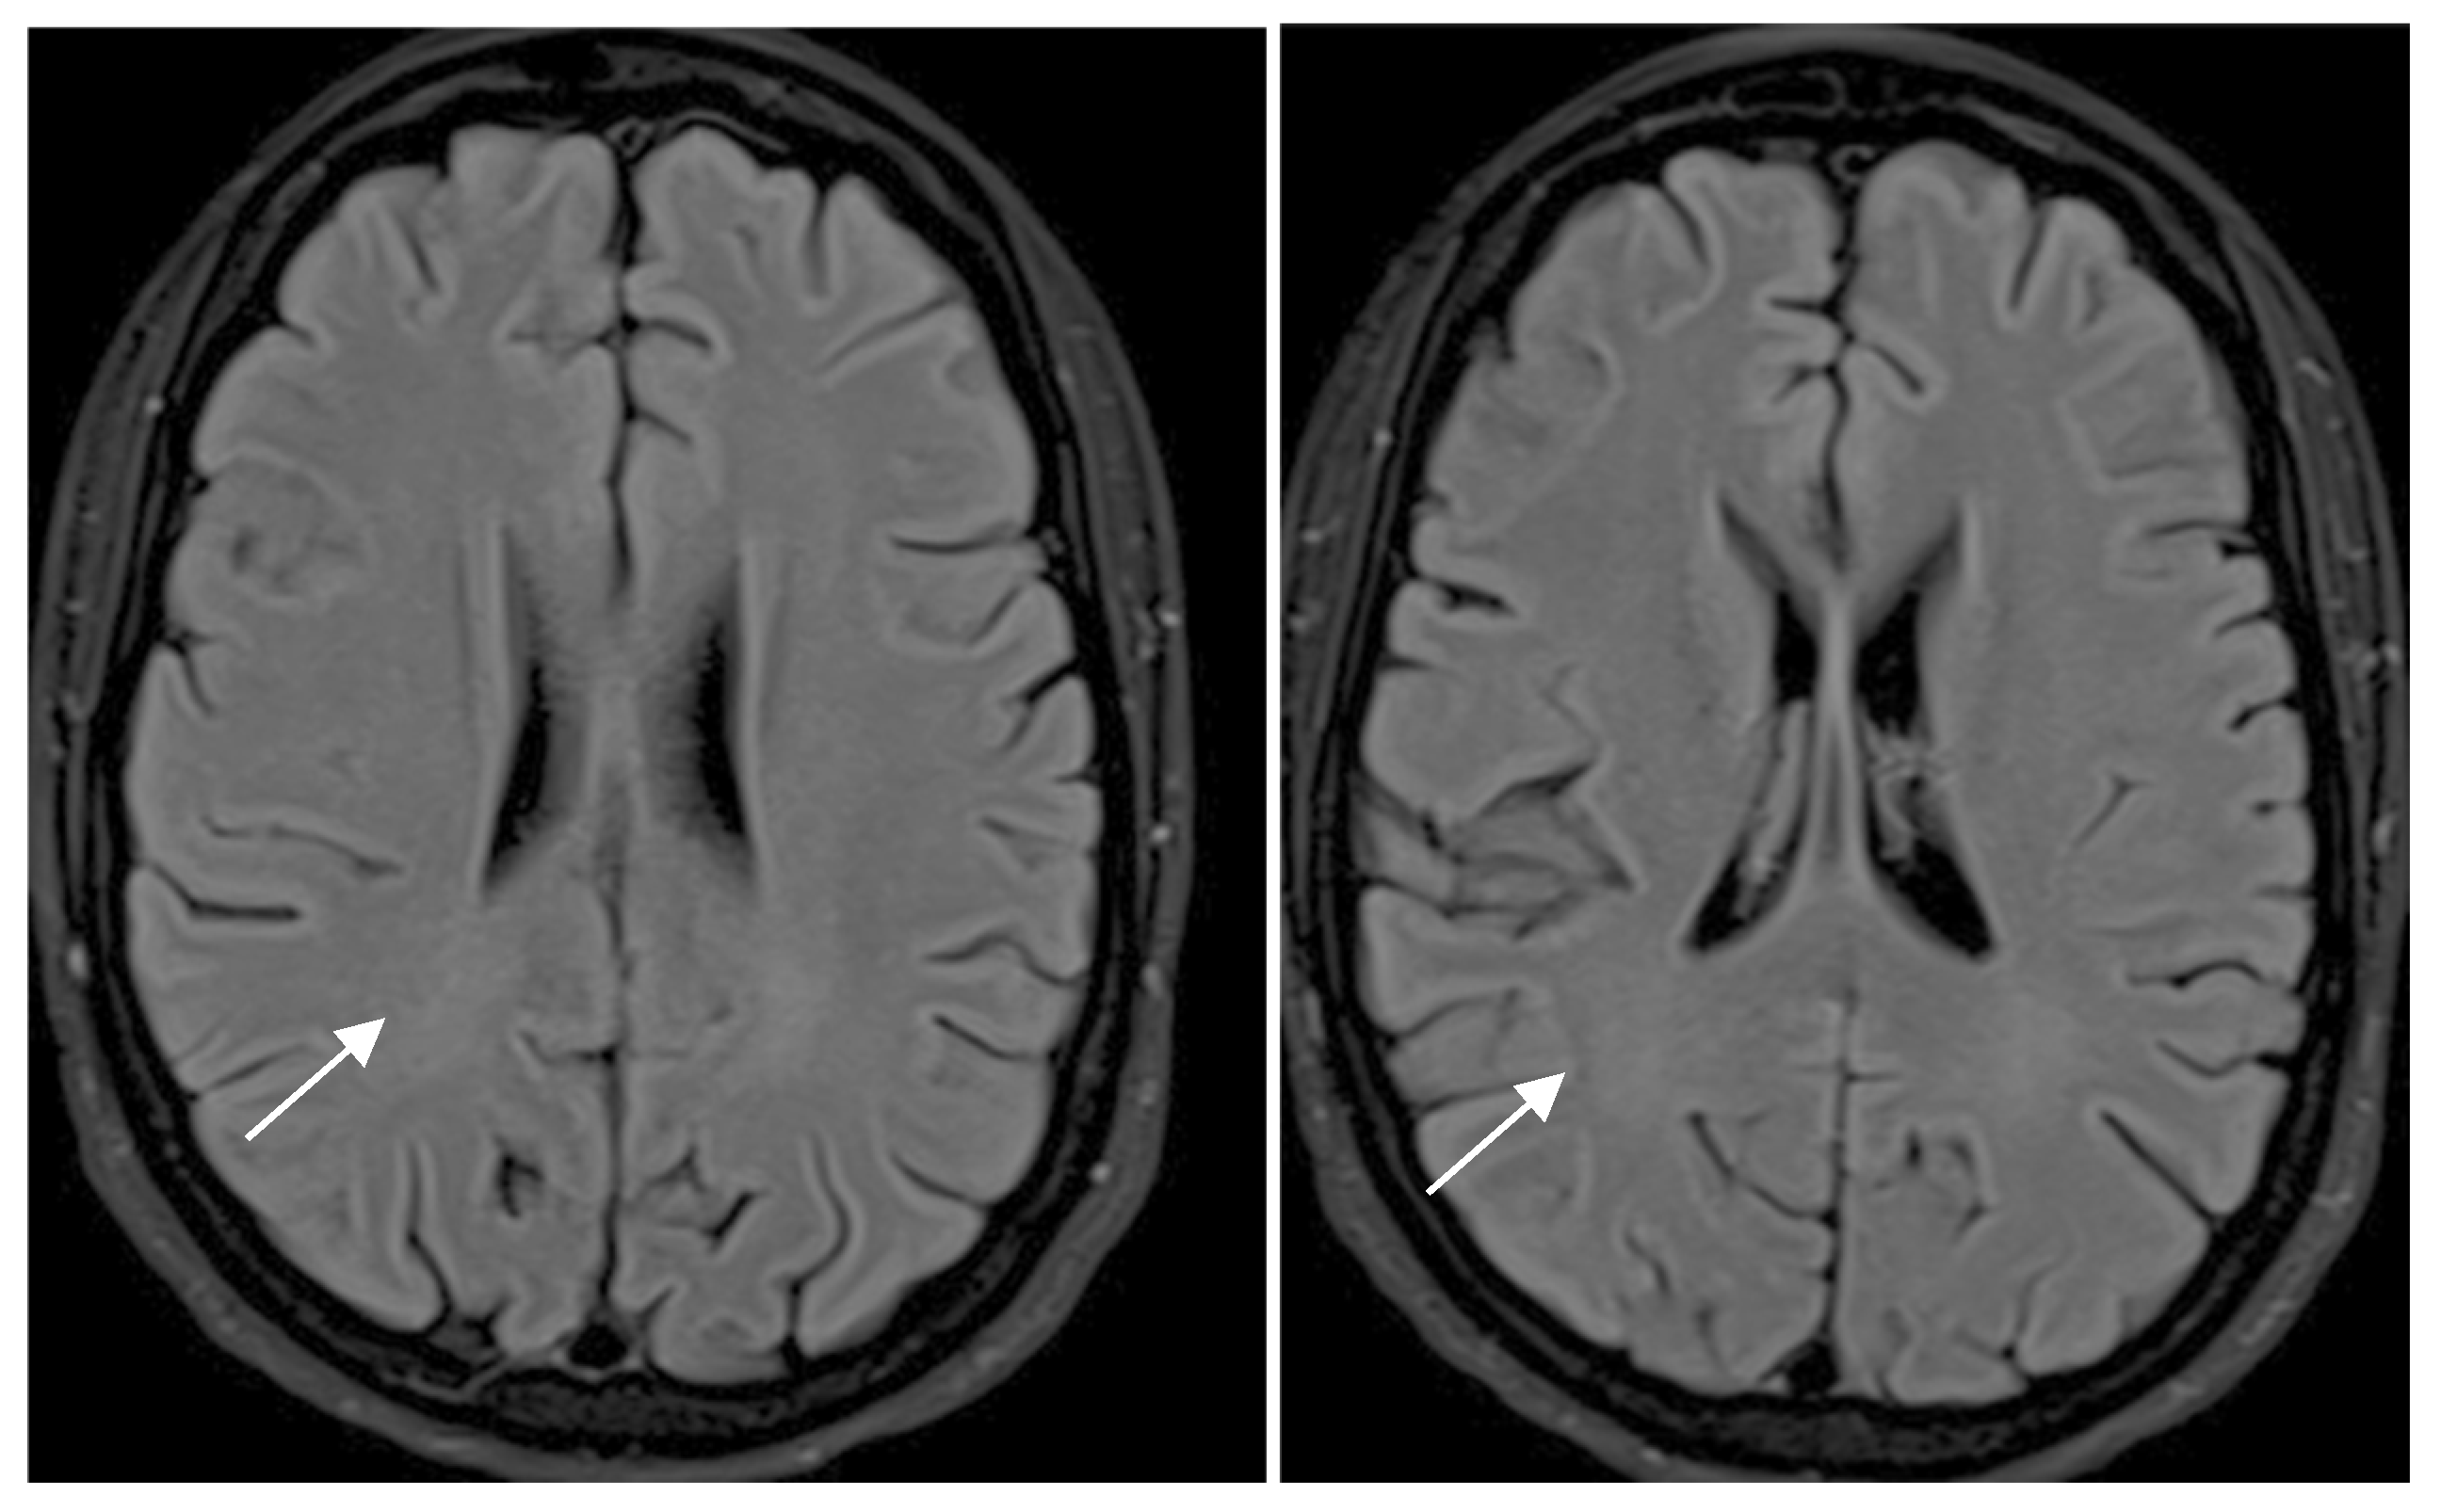

| White Matter Lesions | Rating Scale for MRI |

|---|---|

| 0 | No lesions |

| 1 | Focal lesions |

| 2 | Beginning confluence |

| 3 | Diffuse involvement of entire region, with or without involvement of U fibers |